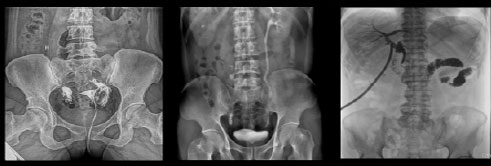

- Применяется в различных клинических рентгенологических исследованиях, таких как рентгенография, цифровая флюороскопия, контрастная и визуализированная точная съемка DR

Рентгенологические исследования: рентгенография больших переломов костей и масштабное физическое рентгенографическое обследование, флюороскопия всех частей тела (грудная клетка, живот и т.д.), пищеводная ангиография, ангиография верхних отделов желудочно-кишечного тракта, полная ангиография желудочно-кишечного тракта, холангиография, Т-образная холангиография, ЭРХПГ, внутривенная пиелография, гистеросальпингография и т.д.